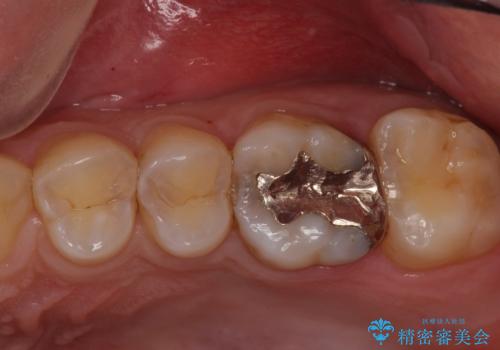

コンタクトカリエスの治療

- 虫歯の検査のために来院された患者さまです。

レントゲンで診査したら、歯と歯の間に虫歯(コンタクトカリエス)が見られたので

e-maxインレーで治療を行いました。